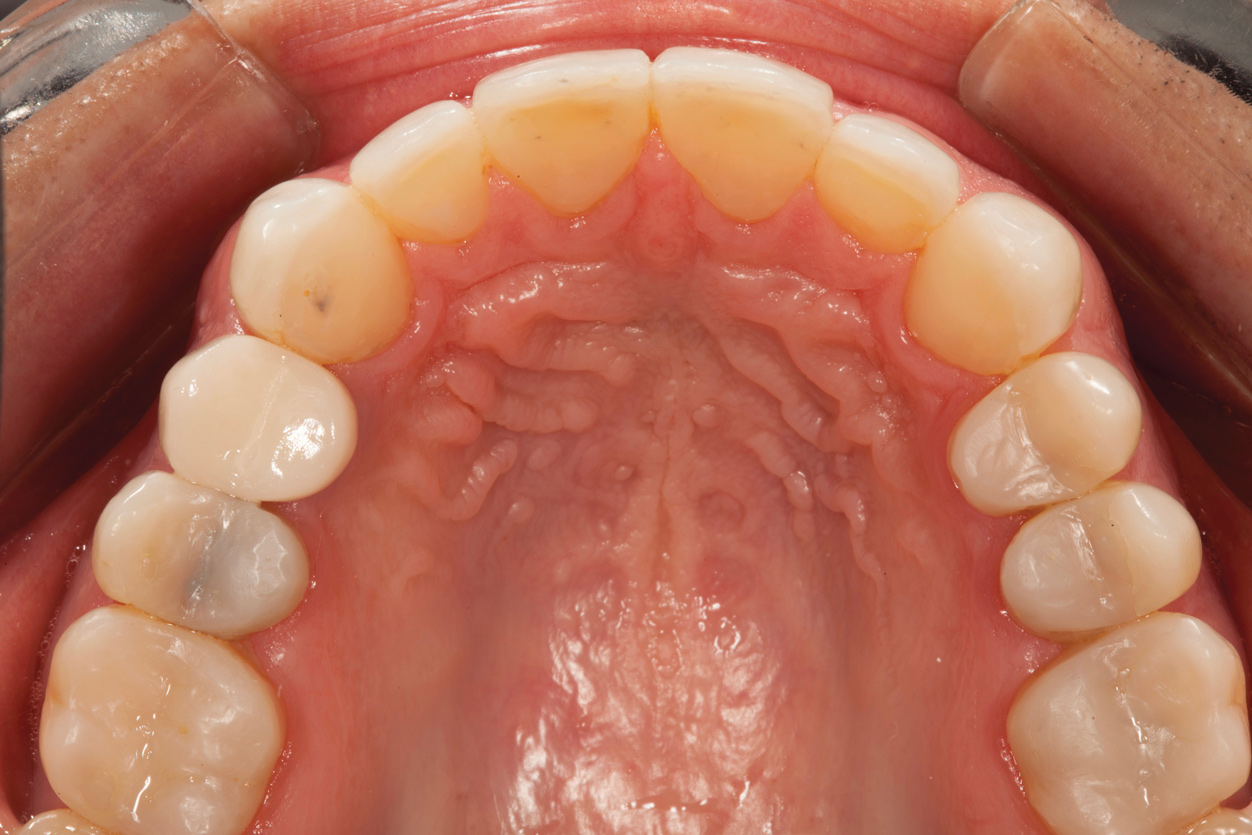

A comprehensive examination was carried out, and preoperative photographs were taken (Figure 1 through Figure 4). The patient presented with fair oral hygiene and slight, generalized tissue inflammation. Caries and defective restorations were detected on teeth Nos. 4, 5, 13, and 14. The crown on tooth No. 12 was showing signs of leakage, and although the endodontic access cavity had been temporarily restored with composite, this endodontic re-treatment was acceptable and the tooth was otherwise symptom-free. Erosion was present on most of the posterior teeth and the cuspids, and abrasion was noted on teeth Nos. 4, 5, 10, 11, 20, 21, 22, 28, and 29. An examination of the patient's muscles, joints, and bite revealed no joint sounds, a normal range of motion, and negative joint load and immobilization tests.

The patient's removable dental orthotic covered the lower bicuspids and first molars. With the orthotic in place, there was shim stock contact on all posterior teeth and on the second molars that were not covered by the appliance. However, there was no incisal overlap and a lack of anterior guidance.9When the orthotic was removed, no more than three teeth touched, and a 2-mm space between the posterior teeth made mastication difficult.

Fig 3. Preoperative occlusal view of lower arch with orthotic in place.

Figure 3

Fig 4. Preoperative occlusal view of upper arch.

Figure 4